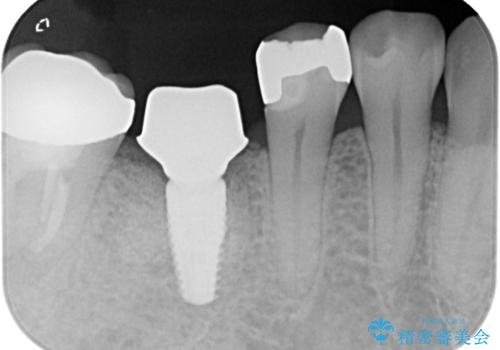

抜歯をしたあと骨が痩せないよう抜歯直後に骨補填材を入れています。

骨が成熟するまで待ち、インプラントを埋入しました。

被せ物はオールセラミッククラウンを被せています。